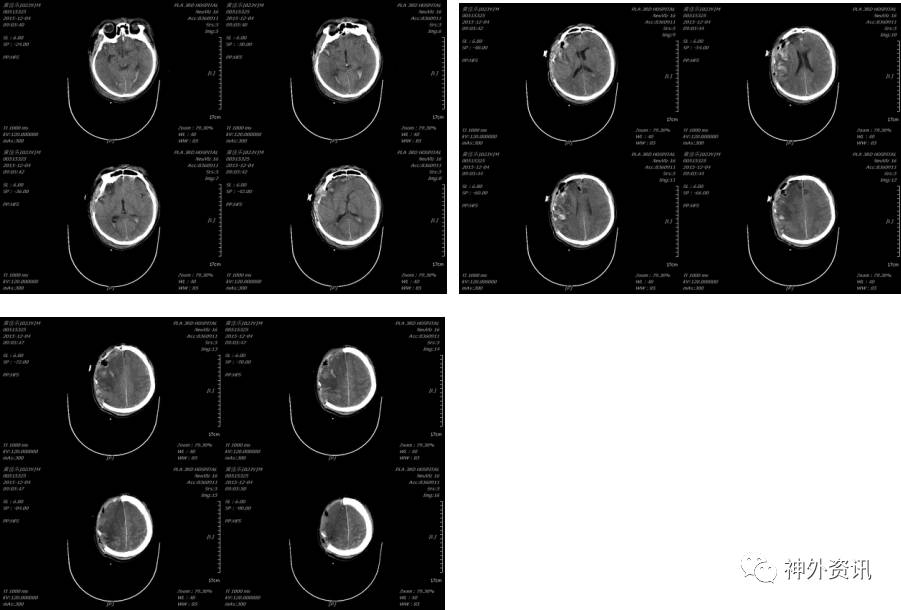

患者术后虽然颅内显示正常,但挫伤出血量大,脑肿胀明显,行二次开颅颅内血肿清除术,术后复查头颅示(2015-12-04 09:05):

术后给予镇痛、镇静、机械通气、脱水、止血、抗感染、目标性体温控制、营养支持等治疗,术后4天复查头颅CT及胸部CT示(2016-12-08 10:39):

患者术后持续昏迷,分别于2015-12-11、2015-12-13及2015-12-18行腰椎穿刺术,脑脊液提示为血性脑脊液逐渐转变为红色脑脊液,期间未发现明显感染迹象。胸部给予反身、叩背、吸痰、重症早期康复、高压氧等治疗,2015-12-18逐渐意识恢复至朦胧,至2016-01-03患者逐步意识恢复至清楚,自动睁眼,配合动作,失语。双侧瞳孔等大形圆,直径各约2.5mm,对光反应灵敏,双肺呼吸音清晰,右侧肢体活动可,肌力Ⅳ级,左侧肢体刺痛反应弱,左上肢肌力Ⅰ级,左下肢肌力Ⅱ级,四肢肌张力正常。期间多次复查头颅CT示见出血吸收,胸部CT好转。